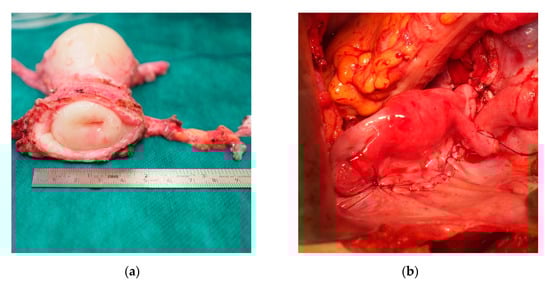

The uterus was transplanted in an orthotopic position in the lesser pelvis with arterial and venous anastomoses to the iliac vessels and vaginal anastomosis to the vault of vagina (Figure 1). Vascular anastomoses were fashioned without the administration of intraoperative heparin. The intended period for the graft in situ and exposure to immunosuppression is 5 years. The ultimate objective is a livebirth of 1–2 children. Completion hysterectomy and withdrawal of immune suppression should be carried out thereafter.

Figure 1.

(a) Uterus graft from a deceased donor during back-table surgery. (b) Uterus graft transplanted in an orthotopic position in the lesser pelvis.